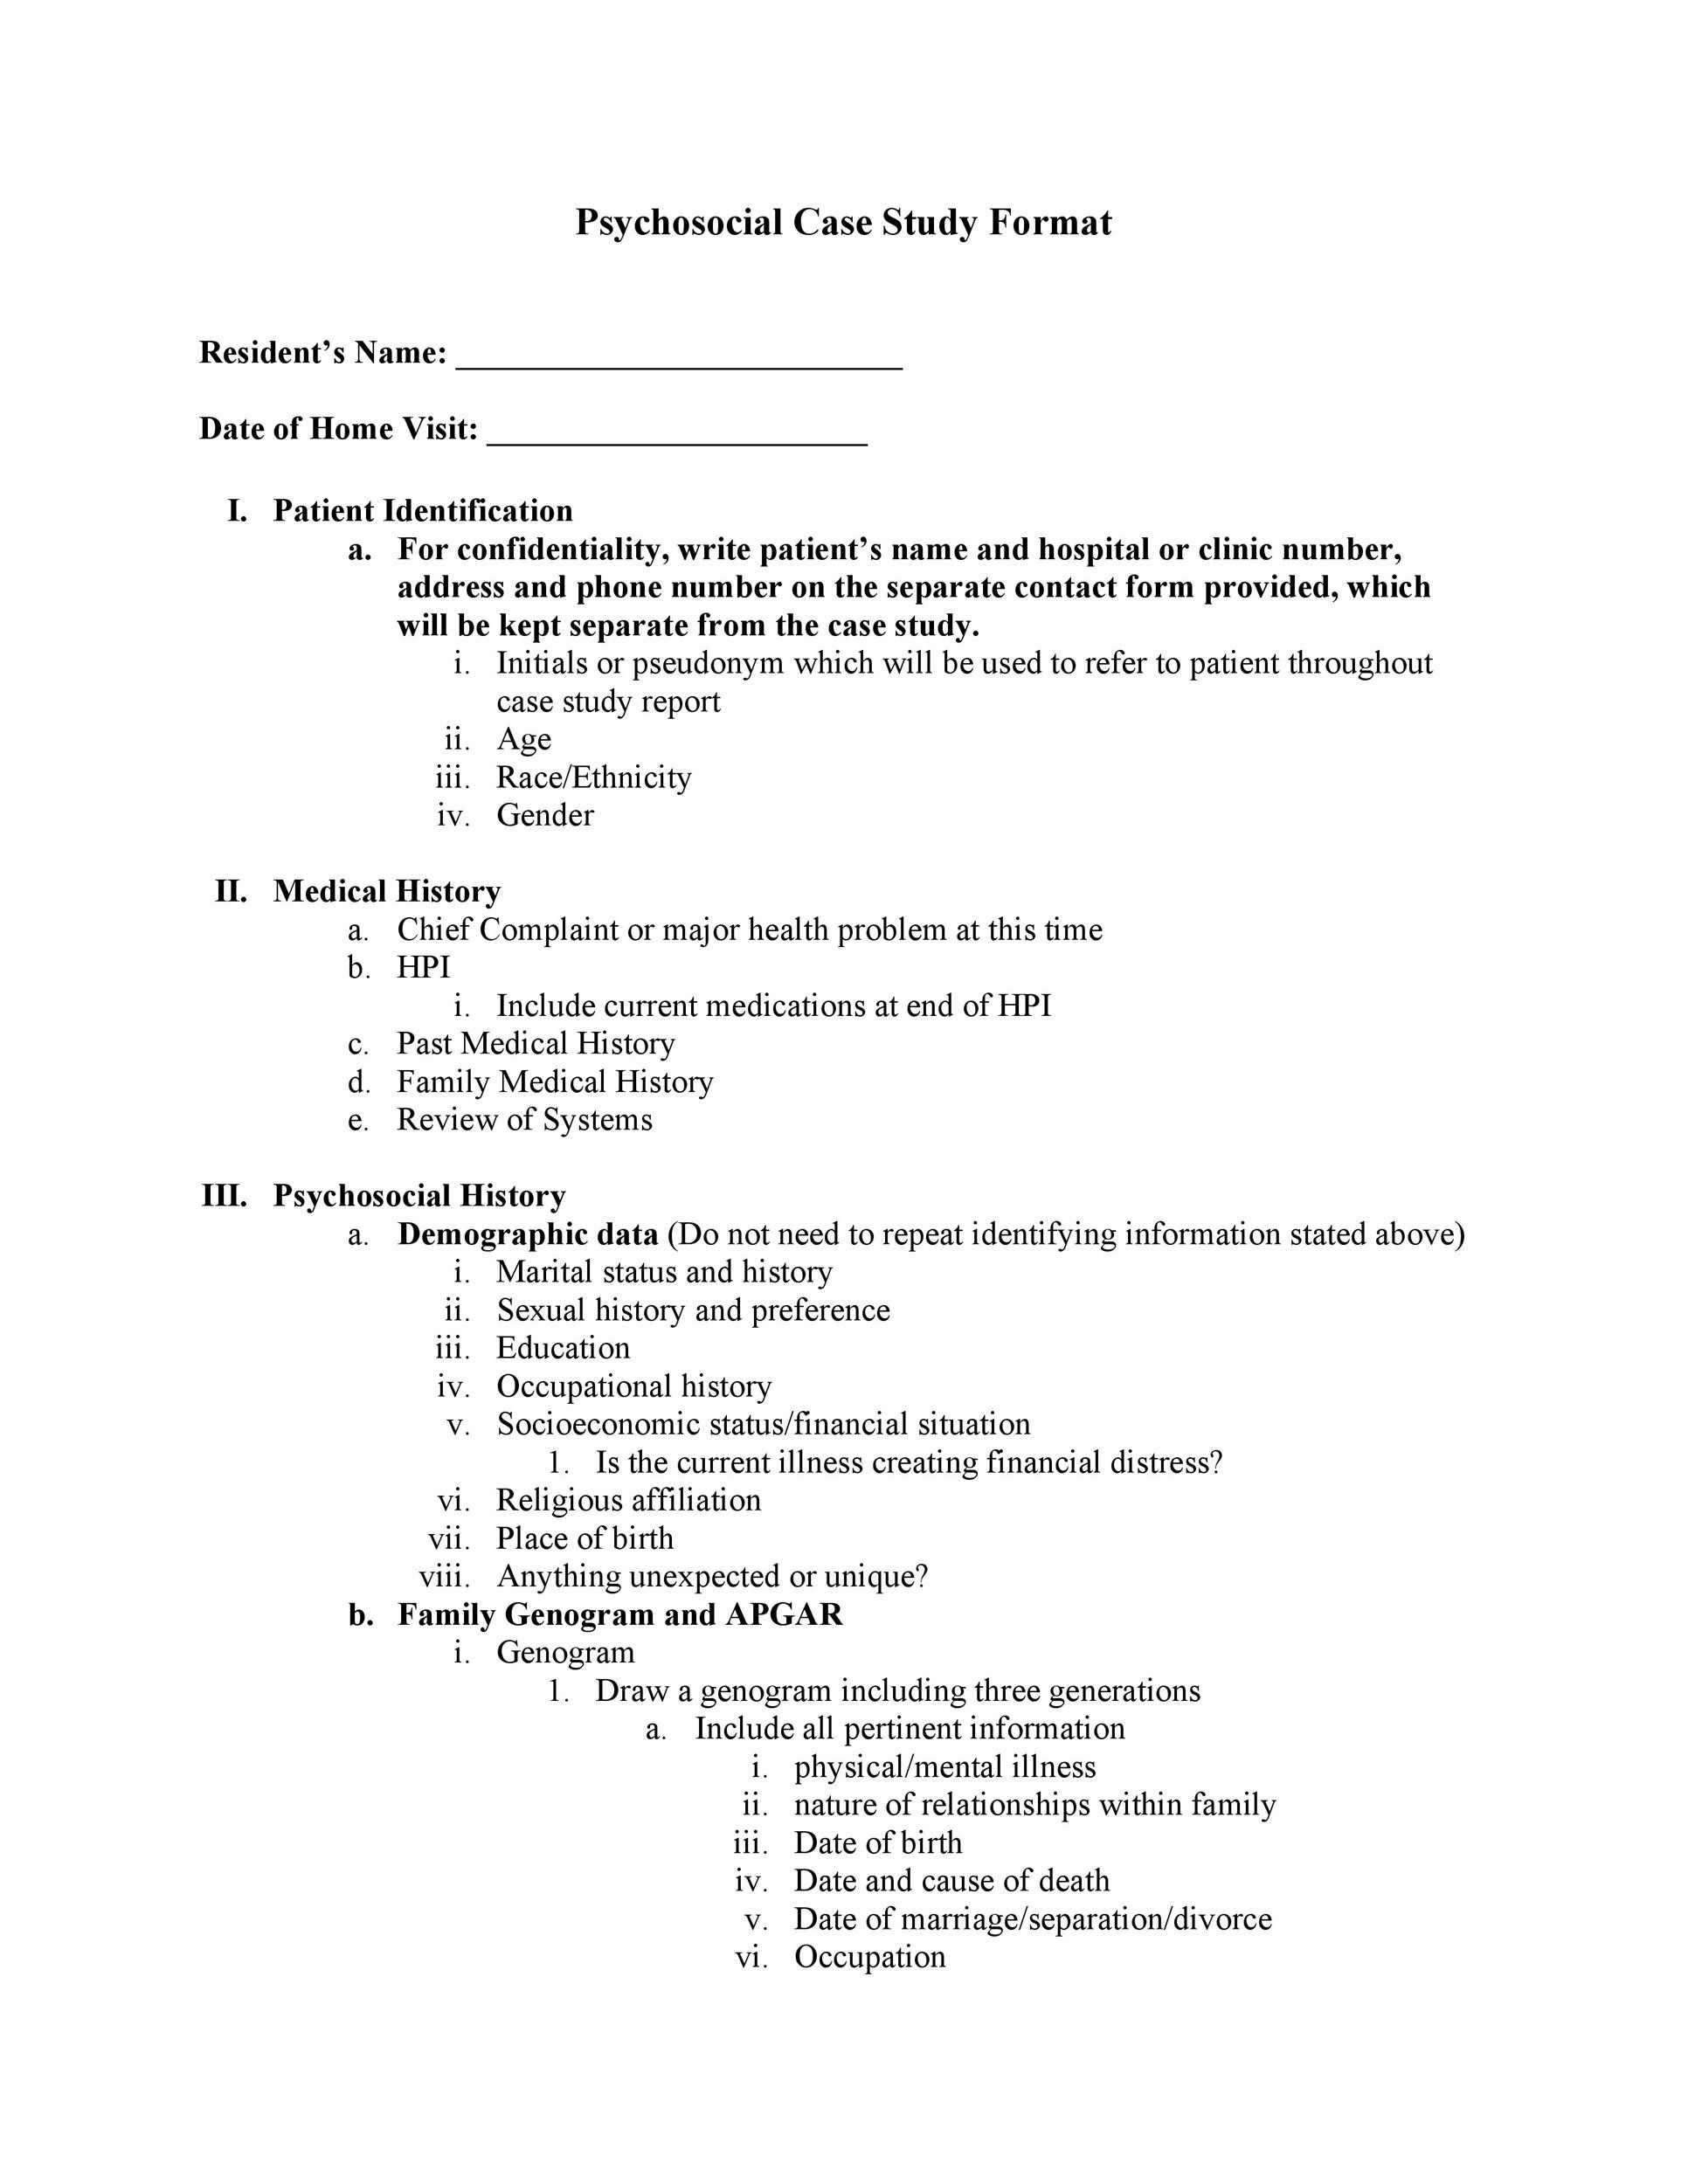

Clinical Case Study Format